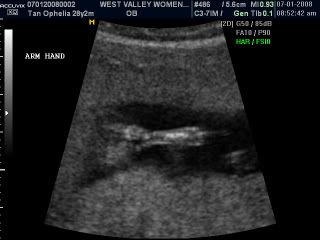

Beanie's little arm...